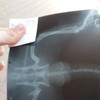

«Клиника скорой ветеринарной помощи» на Профсоюзной улице специализируется на оказании длинного ряда лечебно-профилактических услуг мелким домашним животным. Особое внимание уделяется питомцам, нуждающимся в вакцинации или неотложной помощи. Лаборатория клиники оснащена новейшим оборудованием для комплексной диагностики состояния здоровья животного, способным представить результат обследования в течение 10 минут. В клинике введена система электронного слежения за изменениями в историях болезней пациентов. Обратившись в «Клинику скорой ветеринарной помощи» вы и ваш питомец останетесь довольны высоким качеством обслуживания и профессионализмом сотрудников. Детально ознакомиться с комплексом услуг клиники и узнать о предстоящих акциях вы можете, посетив официальный сайт организации и страничку в социальной сети.

Как оказалось — плюсов нет никаких, нет ни оборудования ни квалифицированных специалистов — одним словом: г. Шахты. Обратились в данную клику в г. Шахты год назад, опухоль на запястье передней лапы у добермана, доктор — Вольвак Андрей Олегович, после осмотра назначил курс противовоспалительных и антибиотики. После прохождения курса, мы обратились повторно с акцентом на то, что ничего не изменилось, опухоль не ушла и даже не уменьшилась, на что доктор — Вольвак Андрей Олеговичнам ответил: Ну раз опухоль собаку не беспокоит, то и волноваться не надо и не надо ничего ковырять и беспокоить эту шишку, собака с этой шишкой проживет долго и счастливо. Мы по своей наивности доверились доктору. В результате всего этого уже через год в ростовской клинике нашему доберману поставили диагноз: саркома мягких тканей и теперь даже операция как и ее исход под вопросом! И единственный вопрос который нам задали в ростовской клинике — ПОЧЕМУ ВЫ НЕ БЕСПОКОИЛИСЬ и не обратились раньше? На что мы ответили — к сожалению мы обращались, но как оказалось не туда куда надо. Учитывая вышеизложенное — внимательнее подходите к выбору клиник, если вам дорог ваш питомец — не лечите его в данной клинике, да и вообще в клиниках г. Шахты.